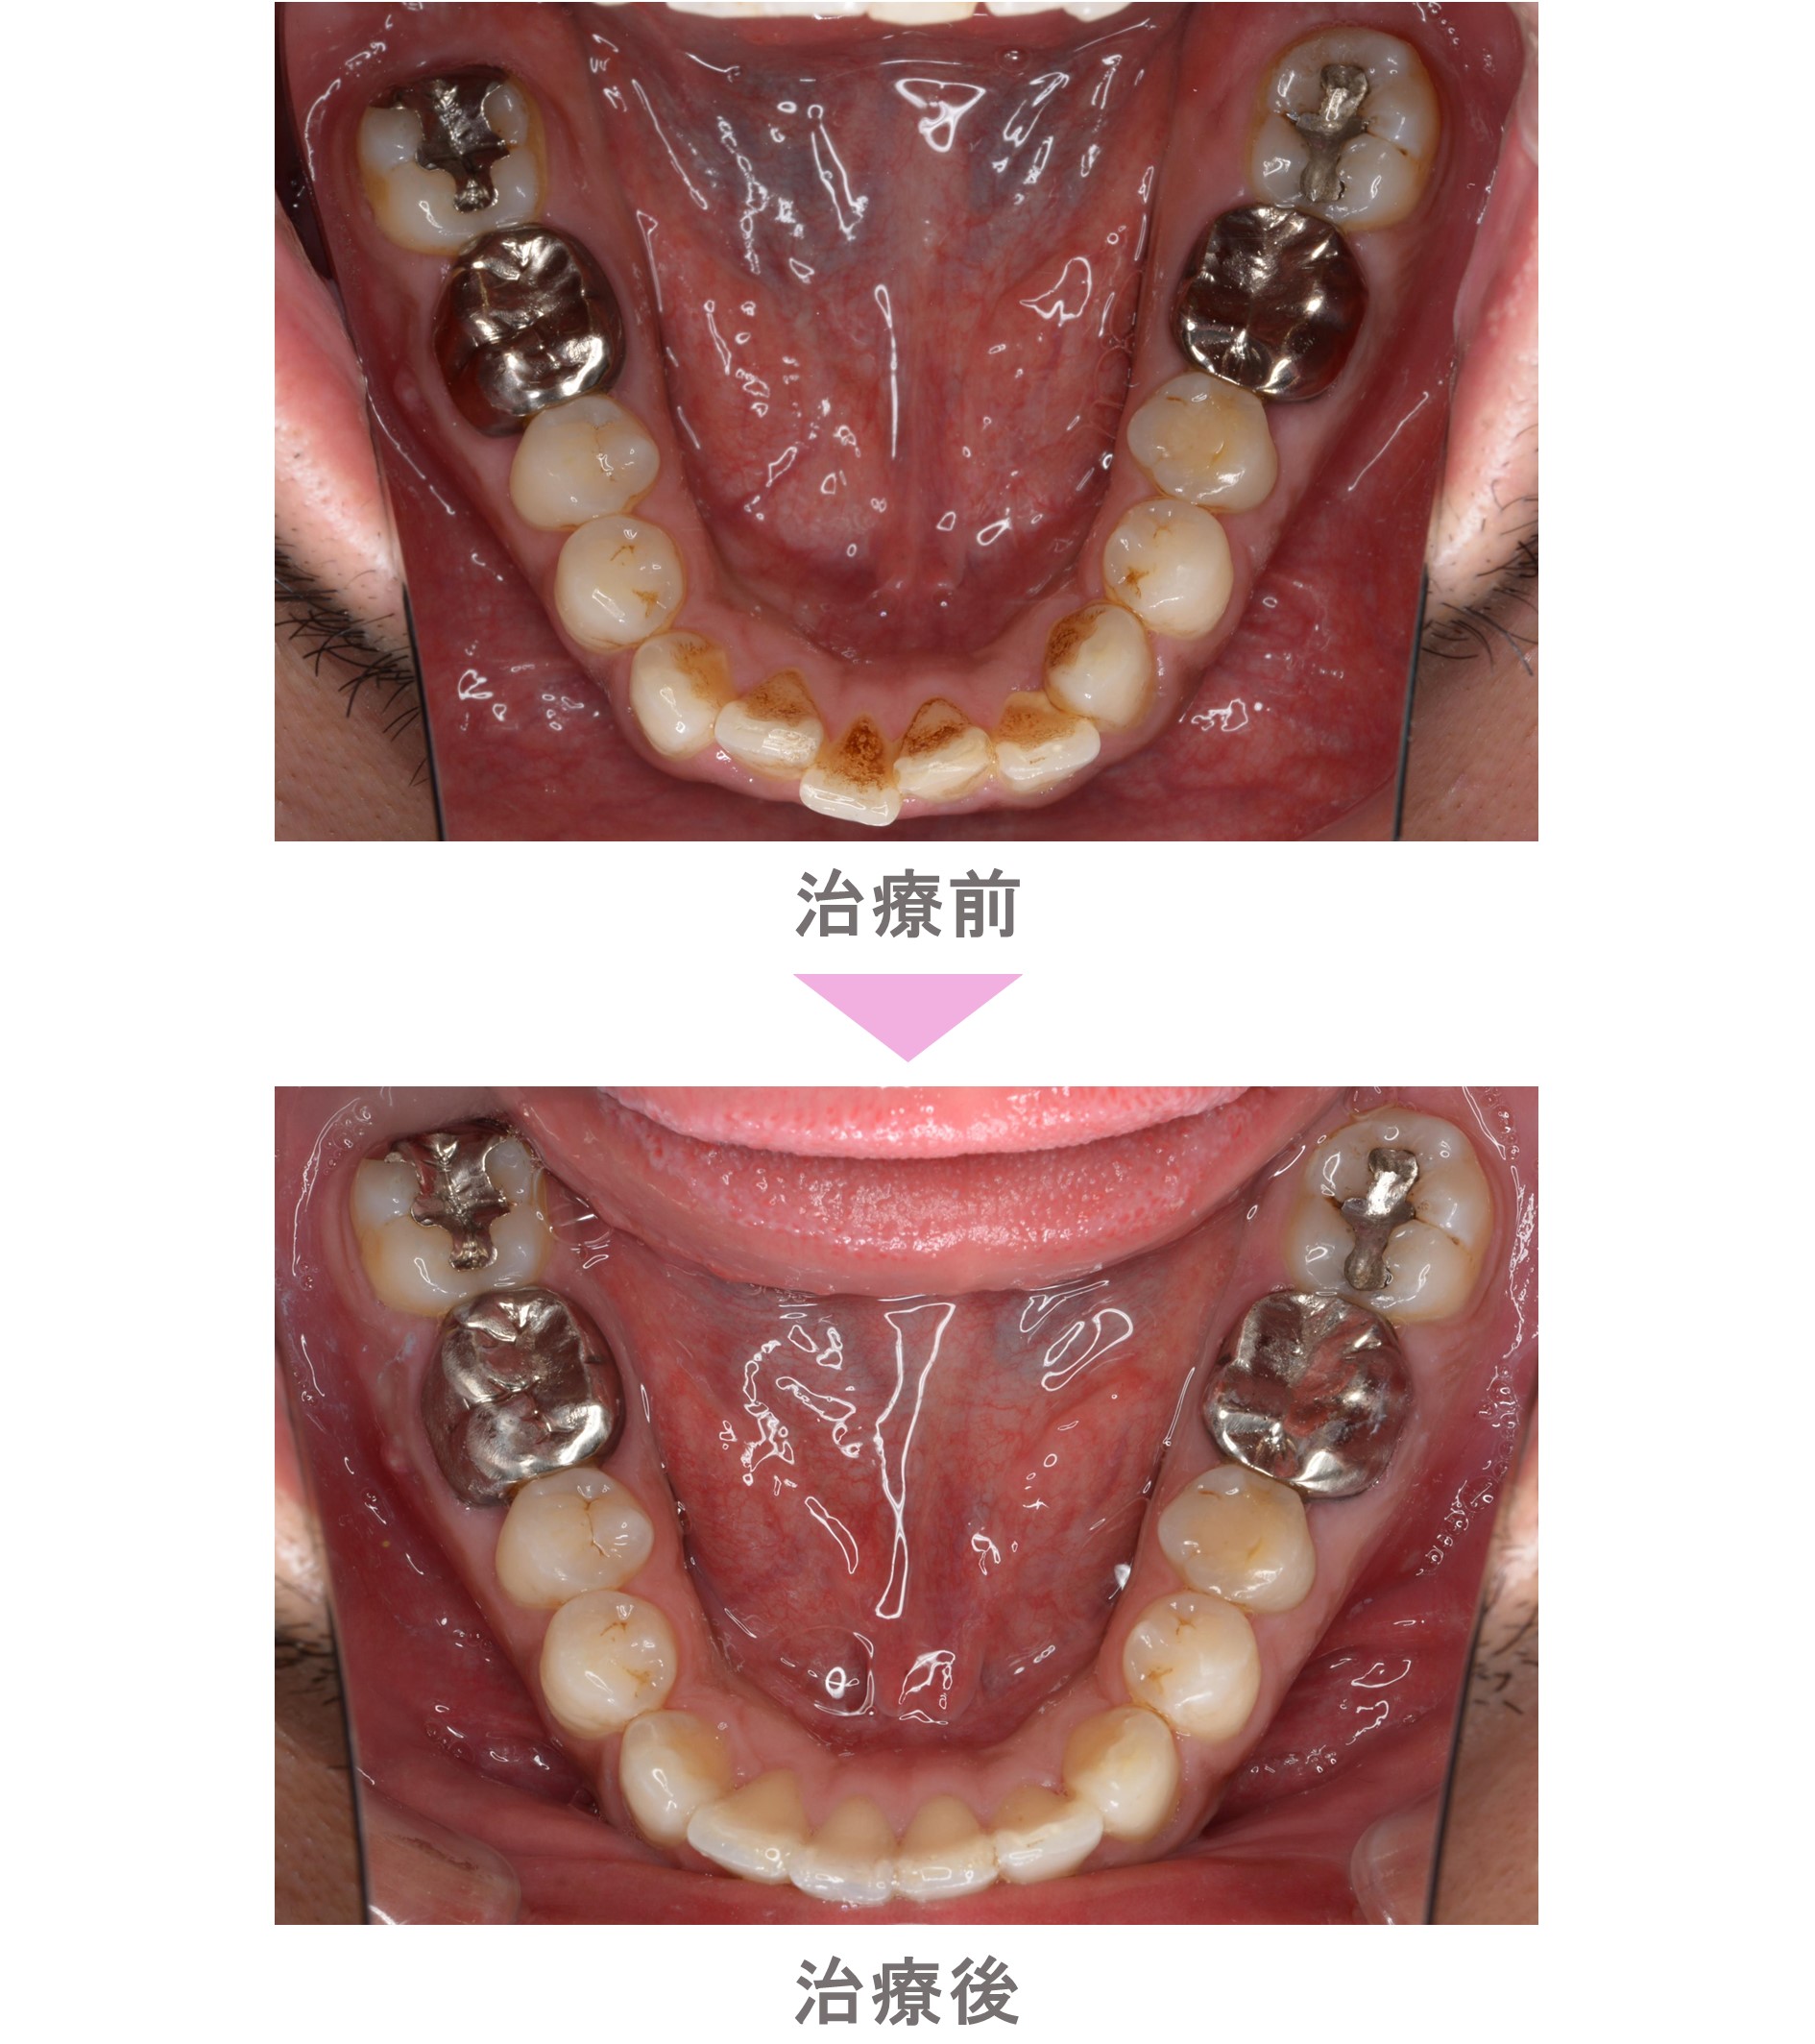

部分矯正(プチ矯正)・裏側矯正(舌側矯正)の症例紹介|叢生(前歯のでこぼこ)の症状|非抜歯による矯正治療|治療期間は6か月(東京都世田谷区・30代男性 )

部分矯正(プチ矯正)の症例のご紹介です。この患者様は、東京都世田谷区内からご来院の30代男性で、叢生(前歯のでこぼこ)の症状がありました。治療法は部分矯正。非抜歯で矯正治療を行い、キレイな歯並びになりました。治療期間は6か月です。